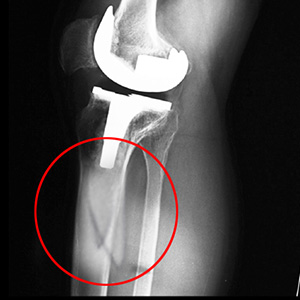

Knee replacement, also called knee arthroplasty, is a surgical procedure in which the worn-out or damaged surfaces of the knee joint are removed and replaced with artificial implants. Any resulting fractures or breaks in the bone around the implant are called periprosthetic knee fractures. These fractures may occur during surgery (intraoperative) or after surgery (postoperative), and usually involve the patella, tibia or the femur (kneecap, shinbone, and thighbone). Women are at higher risk than men.

Diagnosis involves a doctor’s examination followed by injury stabilization to prevent further damage. A traction device is used to keep your leg straight. Your doctor orders an X-ray, MRI or CT scan. Blood tests may also be ordered.

Periprosthetic knee fractures are usually treated surgically, under general or regional anesthesia. The presence of multiple bone fragments, bone cement or weak bones increases the complexity of the surgery. The surgical procedure may be either of the following:

- Joint-Revision Surgery: Some cases of periprosthetic knee fracture are caused by a loose implant. Joint-revision involves the removal of the old implant and placement of a new implant with special components to treat the fracture.

- Open Reduction and Internal Fixation (ORIF): Some cases of periprosthetic knee fractures do not require replacement of the implant and the fractured bone fragments are fixed together with the help of screws.